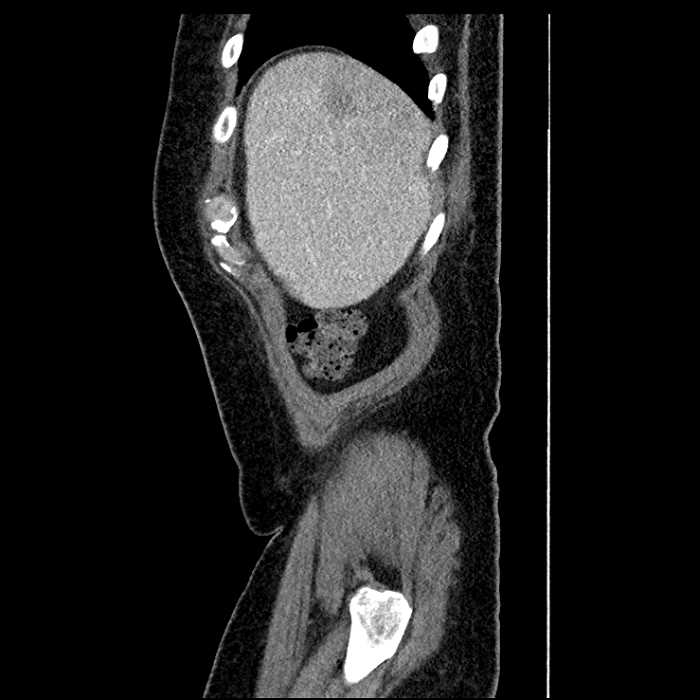

Age: 63

Sex: Male

Indication: Abdominal pain

• Large fluid density structure in hepatic segments 7 and 8 measuring 10 x 7 x 7 cm with internal septation and circumferential ill-defined low density compatible with edema

• Peripherally enhancing subcapsular collections along the anterior margin of the left hepatic lobe measuring 3 x 1 cm and 2 x 1 cm

• Hepatic abscess

Acute sigmoid diverticulitis complicated by a small contained perforation and a large abscess in the right hepatic lobe. Additional small subcapsular abscesses along the anterior margin of the left hepatic lobe.

• The classic CT imaging appearance is a double target sign with internal low density surrounded by an internal enhancing rim (capsule) and a low density external rim (edema)

Hepatic abscess showing the double target sign with low density internally surrounded by a thin inner enhancing rim (red arrow) and ill-defined outer low density rim (yellow arrow). Blue arrow indicates an internal septation. Red arrows: additional smaller subcapsular abscesses. Red arrow: focal contained perforation associated with diverticulitis.